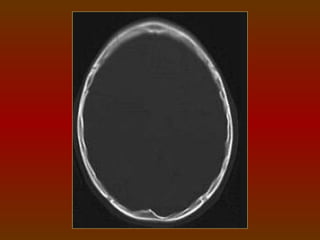

TC CRÂNIO AXIAL

COM JANELA ÓSSEA

FILTRO DURO OU ÓSSEO

É o filtro com maior nitidez e definição da imagem realçando

as bordas, margens ou estrutura anatômica.

Utilizado para estruturas com grande densidade (osso).

Exemplos: crânio – suspeita de fraturas.

TCE: utilizar o filtro como rotina.